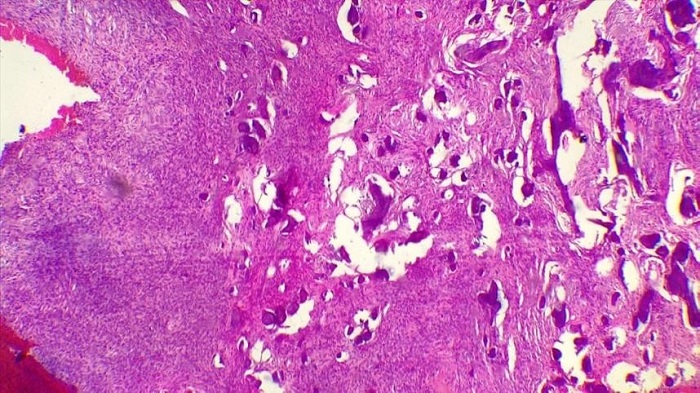

Previo a la realización del tratamiento, se obtuvo el consentimiento informado del paciente y se realizó una biopsia incisional de la lesión. El estudio histopatológico identificó una lesión tumoral fusocelular y tejido conectivo denso con un patrón esteriforme que rodeaba trabéculas óseas con una palizada de osteoblastos, con calcificaciones y tejido osteoide, moderadamente celular y sin clara atipia. La lesión estaba acompañada de células gigantes y áreas de hemorragia que sugerían un FO de la variante juvenil (figura 4).

Se decidió eliminar la lesión, extraer los dientes comprometidos (segundo premolar y primer molar inferiores izquierdos) y efectuar remodelado. Para comprobar la exéresis total de la lesión (figura 5) se tomó una radiografía y se envió nuevamente a análisis de patología, cuyos cortes mostraron una lesión fibrósea benigna constituida por numerosas trabéculas óseas curvilíneas, con apariencia de “letras chinas”, sin recubrimiento osteoblástico e inmersas en un estroma de tejido fibroso moderadamente celular, sin atipias. El diagnóstico fue DF (figura 6).

Por tal razón, se decidió solicitar análisis inmunohistoquímico que mostró ausencia de reactividad en los marcadores de citoqueratina AE1-AE3, P63, S100, con un índice de proliferación celular (KI67), en el que los hallazgos morfológicos mostraron una lesión fibrósea constituida por un componente fusocelular con tejido conjuntivo fibroso con variable grado de celularidad y trabéculas óseas, algunas de apariencia inmadura, y formación de especie de glóbulos acelulares de apariencia semejante al cemento, lo que dio lugar a una lesión fibrósea sin atipia. En el control posoperatorio se observó mejoría de la simetría facial y cicatrización de tejidos blandos. En el control más reciente a un año se identificó regeneración ósea casi en su totalidad, sin alteraciones estructurales, ni cambios óseos.